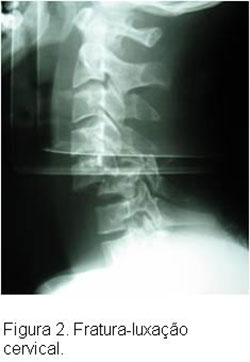

O tratamento do doente vítima de TRM inicia-se na abordagem inicial do paciente politraumatizado, segundo especificações do ATLS , tomando- se os cuidados necessários quanto a imobilização da coluna a fim de se evitar a progressão ou mesmo o surgimento de lesões neurológicas. Após a estabilização do paciente e realização diagnóstica de TRM com exame físico e exames secundários de imagem como Rx, TC ou RM cervical, deve-se proceder a estabilização da lesão cervical, geralmente com o uso de tração em halo craniano, até a programação do tratamento definitivo, que geralmente consiste na redução cruenta da fratura e fixação interna da mesma.Caso o paciente tenha sido atendido nas primeias 8 horas após o trauma deverá ser instituído a corticoterapia, salvo os pacientes com contra-indicações, segundo protocolo instituído pelo NASCISIII, a fim de evitar possíveis lesões secundárias à medula.Este protocolo consiste na aplicação de metilpredinisolona na dose de 30mg/kg ev na primeira hora, seguido de 5,4mg/kg/hora nas próximas 23hs, isto quando paciente chega ao hospital dentro de 3hs do trauma. Quando chega entre 3-8hs, manter esquema de 5,4mg/kg/hora por 48hs. Após 8hs não realizar corticoterapia. Contra-indicações para corticoterapia: gravidez, criança, imunossuprimido, fx exposta, infeccção grave ou risco de vida.Cuidados: monitorar PA, glicemia, e realizar proteção gástrica.